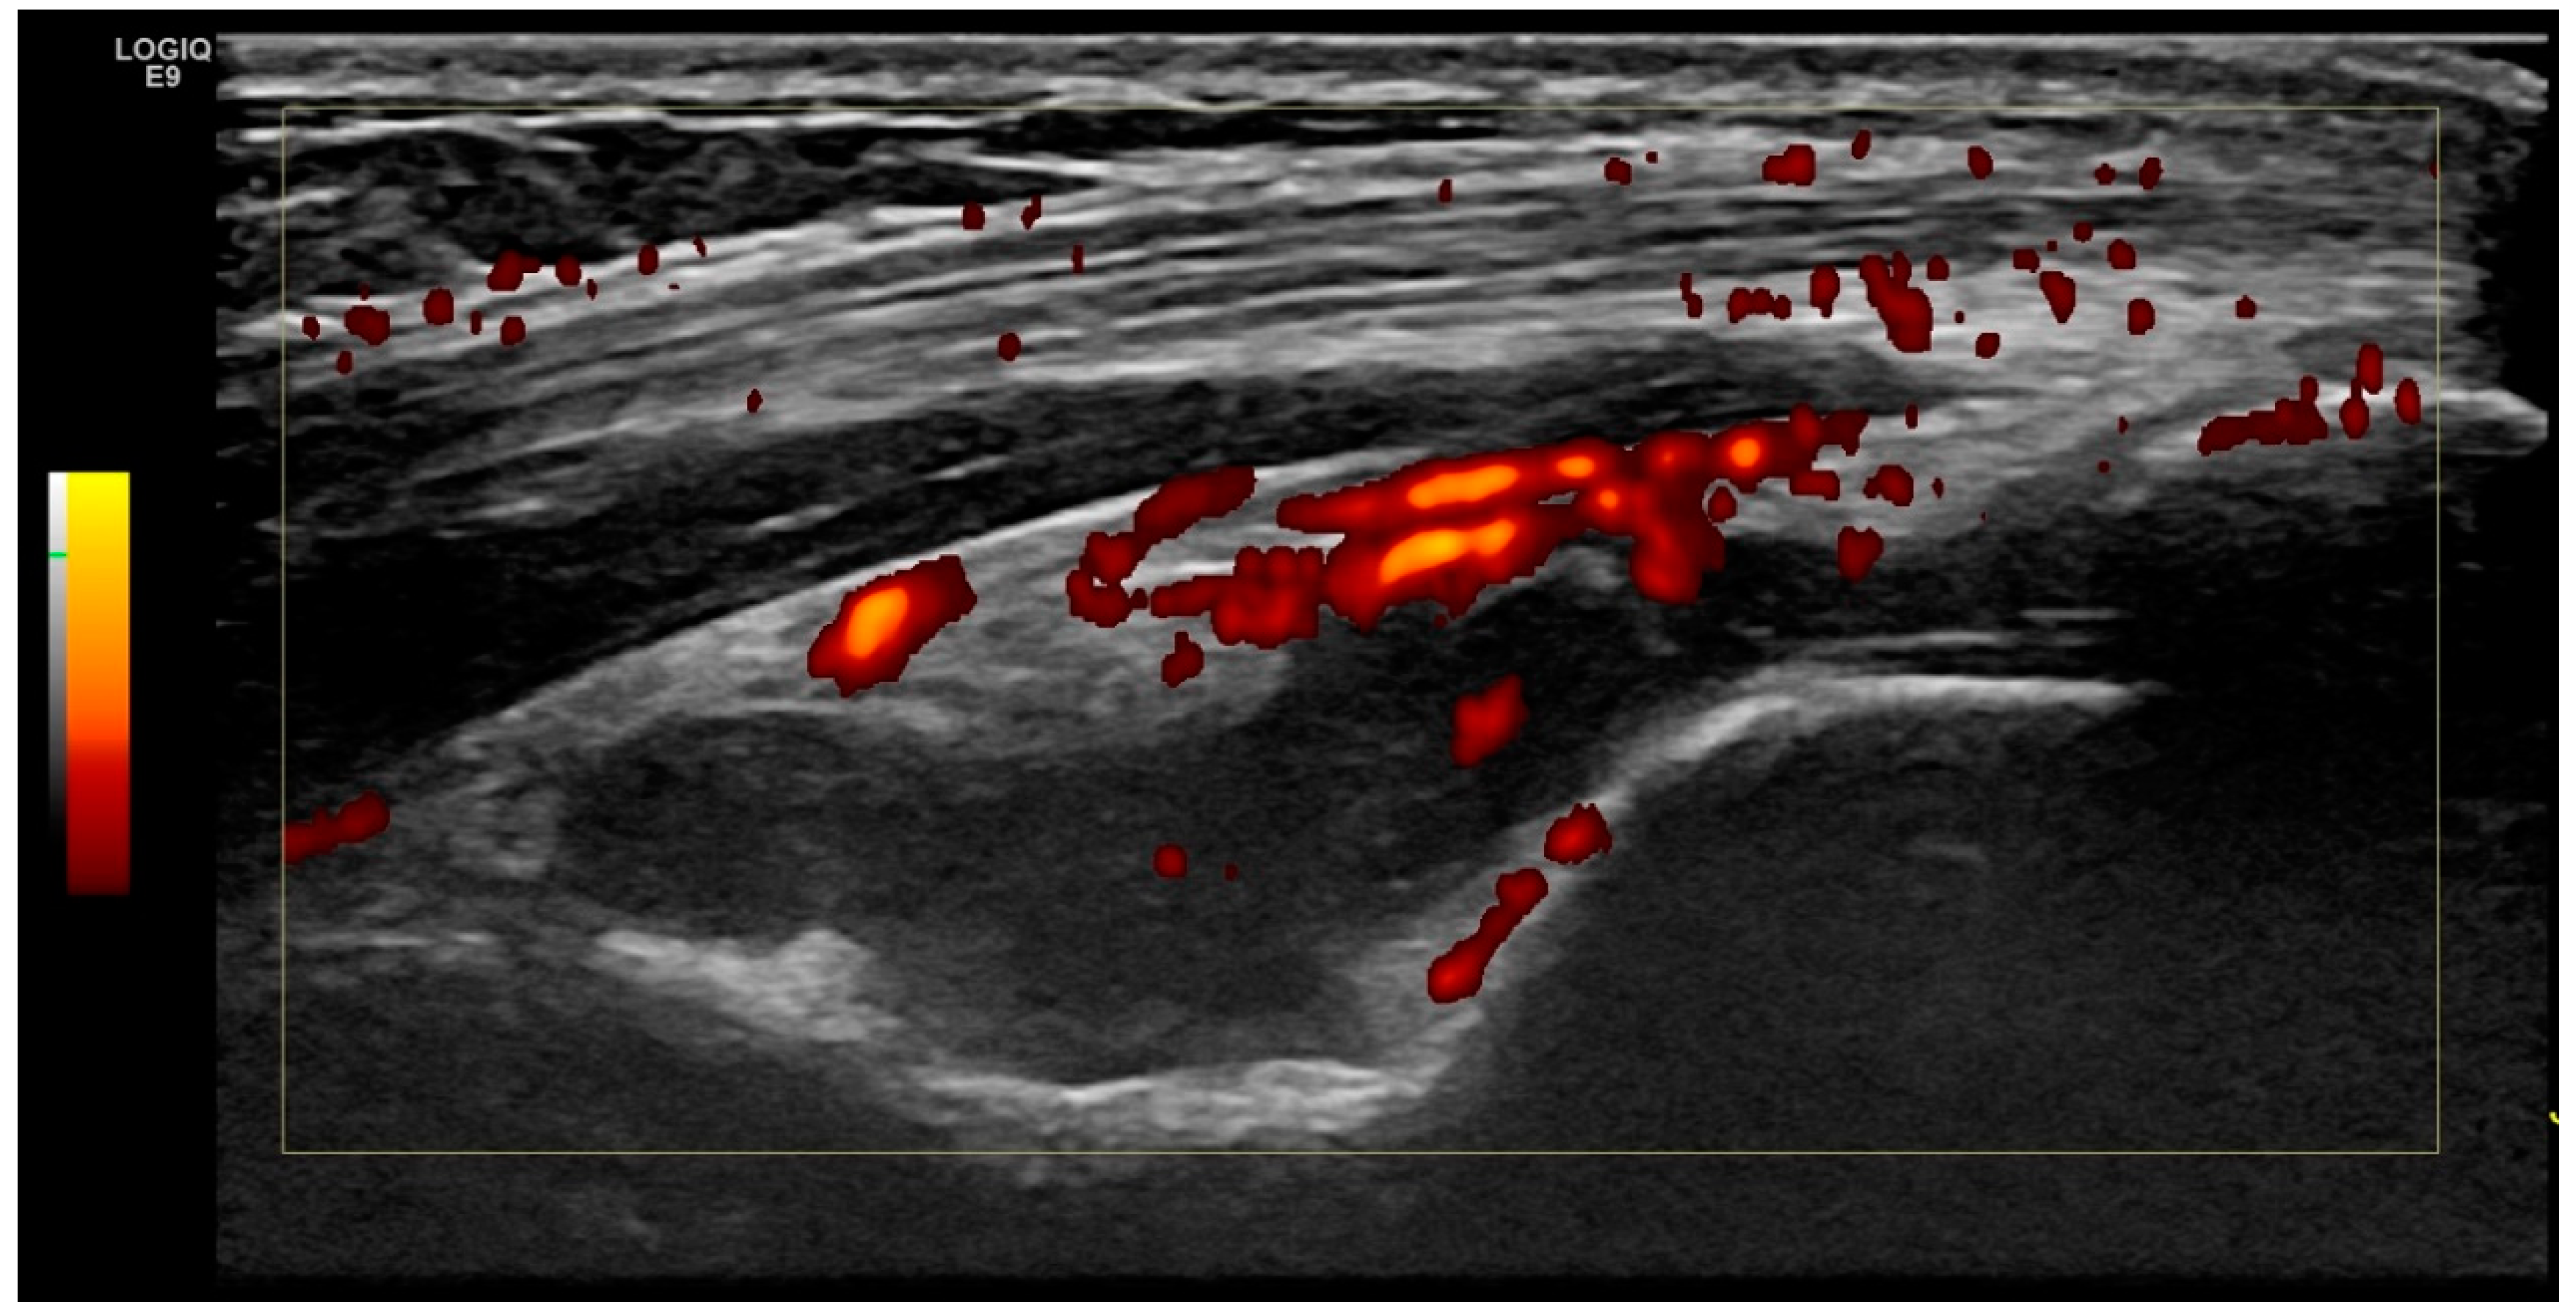

2.2. Ultrasound Examination

2.4. Definition of Elbow Joint Arthritis and Enthesitis

| Any Joint effusion | 42 (41.20%) | 40 (39.20) | 26 (25.00%) | 6 (12.00%) | 4 (8.00%) | 2 (4.00%) |

| Hypervascularisation | 4 (3.90 %) | 3 (2.90 %) | 0 (0.00%) | 0 (0.00%) | 0 (0.00%) | 0 (0.00%) |

| Ultrasound arthritis definition (Effusion ≥Grade 2 and/or hypervascularisation) | 27 (26.47%) (grade > II: 25, hypervascularisation: 2) | 25 (24.51) (grade >II: 24, hypervascularisation: 1) | 16 (15.68%) | 0 (0%) | 0 (0.00%) | 0 (0.00%) |